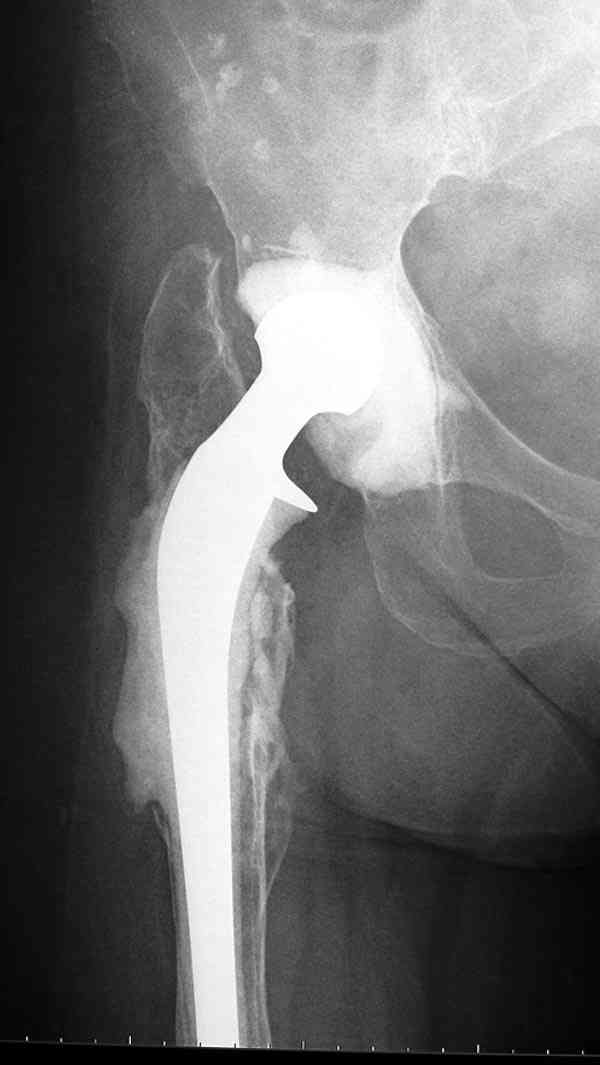

Больному выполнено тотальное эндопортезирование левого ТБС имплантатом Aesculap 05.02.07. В анамнезе в 1988 году травма при ДТП, оперирован в г.Москва - производился синтез заднего края шурупами с аутопластикой. После произведенного эндопортезирования, через 3 нед после операции у больного открылся свищ в области послеоперационного рубца с прозрачным отделяемым желтоватого цвета. Болей и повышения температуры не было. При посеве выявлен Enterococcus faecalis - умеренный рост. Больному было выполнено иссечение свищевого хода (доходил до зоны эндопротиеза), дренирование. Промывался в течение 12 дней растворами антисептиков. Швы сняты на 14 сутки после операции. В тот же день вновь открылся свищ на прежнем месте. Болей и температуры нет. В настоящее время я промываю свищевой ход раствором йодопирона - динамика слабоположительная (объем полости не уменьшается, однако отделяемого практически нет). Протез стабилен. Больной активен. Ходит с костылем. Болевого синдрома нет. Что подскажете? Бился ли кто с такой тварью как Enterococcus faecalis? И кто кого победил? Заранее Всем признателен за советы!!!

Так что вместе ожидания, можно было бы рассмотреть предлагаемый вариант, потом, если это возможно было бы интересно посмотреть на рентгенологическую картину.